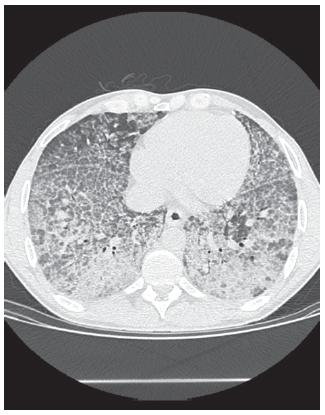

מבחני הדמיה

בדיקת CT של הריאות במקרי COVID-19 מראה הצללות זכוכית חול (ground glass opacities), דו-צדדי רב-אונייתי לעיתים עם מורפולוגיה עגולה או דפוס "5". כמו כן מזהים crazy paving וקונסולידציה באזורים פריפריים או פוסטריוריים. בנוסף נצפתה הגדלה של כלי דם סב-סגמנטליים מעל ל-3 מ"מ באזורי הצללות. עם זאת, CT ריאתי אינו מומלץ כאמצעי אבחון של COVID-19, בגלל הספציפיות הנמוכה של ממצאי CT אלה (Salehi וחב' ב-Am J Roentgenol, ו-Lee וחב' ב-Lancet משנת 2020).